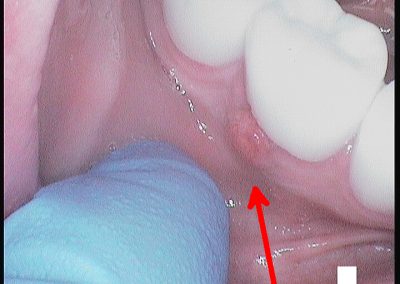

Before commencing the treatment, a local anaesthetic is administered and later a protective non-latex rubber sheet is placed around the tooth to prevent saliva contaminating the tooth and at the same time improves patients comfort.

An access cavity is placed on the surface where the patient bites, to reach the root canals of the tooth. Once all the canals are identified, small files are used to remove the infected pulp.